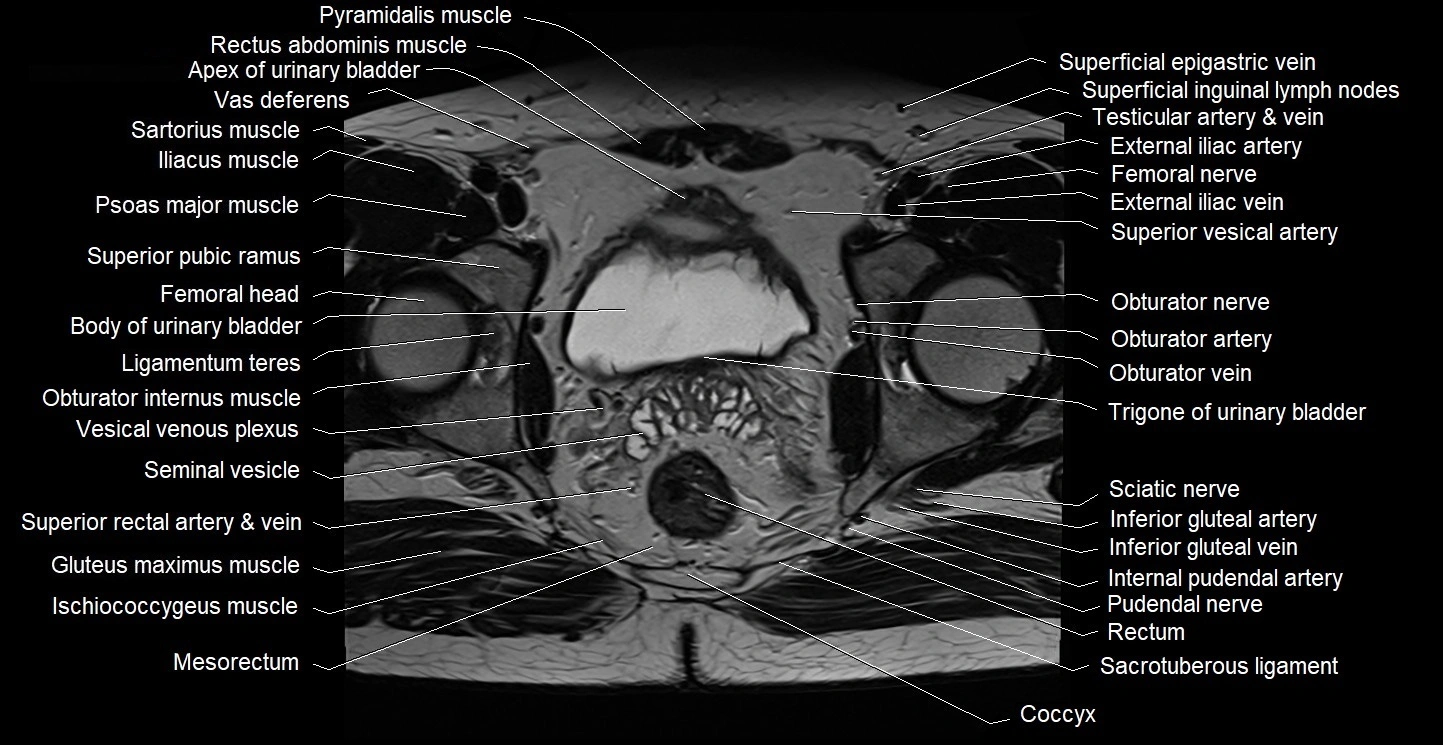

- Apex of urinary bladder

- Body of urinary bladder

- Coccyx

- Gluteus maximus muscle

- Ischiococcygeus muscle

- Mesorectum

- Obturator internus muscle

- Obturator nerve

- Obturator vein

- Piriformis muscle

- Pudendal nerve

- Rectum

- Sacrotuberous ligament

- Sciatic nerve

- Seminal vesicle

- Superficial inguinal lymph nodes

- Superior vesical artery

- Trigone of urinary bladder

- Vesical venous plexus